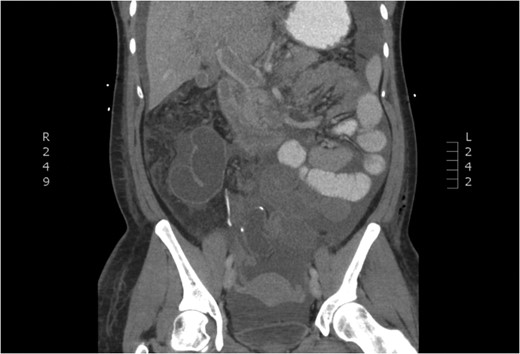

Portal vein thrombosis (PVT) has been recently documented after a variety of laparoscopic surgeries. Although it is well established in splenectomies, its prevalence in other laparoscopic procedures is rare. PVT in colectomies has been associated with inflammatory processes, such as ulcerative colitis and diverticulitis. We report a case of postoperative PVT following a total abdominal colectomy for colonic inertia. A 27-year-old female underwent an uneventful elective laparoscopic total colectomy with ileorectal anastomosis for colonic inertia, and presented on postoperative day (POD) 3 with obstipation, abdominal distention and emesis. Her abdominal pain increased on POD 4 and computed tomography revealed PVT. PVT following laparoscopic surgery is rare in cases not involving the spleen. Although previously seen in colectomies for inflammatory conditions, it can present after colonic inertia. A high index of suspicion should be maintained to diagnosis this rare complication.

The patient presented to the emergency room the evening of POD 3 with emesis and obstipation. Her vital signs and laboratory values were normal. An x-ray showed small bowel dilation and she was readmitted for postoperative ileus. A nasogastric tube was placed and the patient was started on IV fluids. Upon worsening pain and tachycardia on POD 4, a computed tomography (CT) scan with triple contrast was obtained. The CT scan showed evidence of PVT (Figs 1–3). The patient was transferred to the ICU and started on a therapeutic heparin. She improved clinically and was discharged home with rivaroxaban on POD 8. A hematologic evaluation was negative for disorders of factor V Leiden, antithrombin III, homocysteine and cardiolipin.